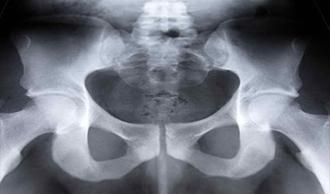

osteitis púbica

La osteítis púbica es un trastorno que afecta a la sínfisis púbica, donde los huesos de la cadera se unen en la parte delantera. A menudo se produce en los deportes que requieren esprintar, dar patadas y hacer cambios bruscos de dirección, como el atletismo, el fútbol y el tenis.